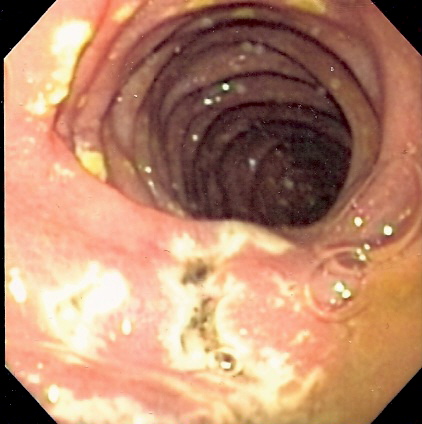

Se diseñó y se validó una escala de síntomas de fácil aplicación para la detección de una enfermedad por reflujo gastroesofágico (ERGE). Los investigadores, de acuerdo con los resultados de la escala, exploraron cinco posibles puntos de corte para medir el constructo ERGE. En esta tabla, se pueden apreciar la sensibilidad (SE), especificidad (ES), valores predictivos positivo o negativo (VPP, VPN), razones de probabilidad positivo o negativo (RPP, RPN) y área bajo la curva (ABC) para cada punto de corte.

ERGE 1 2 3 4 5

SE % 100 95.6 91.6 84.4 73.3

ES % 72.9 86.4 94.9 96.6 98.3

VPP 91.8 95.5 98.2 98. 99.3

VPN 100 86.4 78.9 67.1 55.2

RPP 3.69 7.03 17.96 24.8 43.4

RPN 0 0.05 0.89 0.16 0.27

ABC 50 90.9 93.3 90.5 86

Para este ejemplo, el punto de corte recomendable sería el punto 3, debido a un adecuado balance entre sensibilidad, especificidad, VPP y VPN, así como entre RPP y RPN. Por otra parte, con este punto de corte, se verificó que el área bajo la curva es la mayor y el hombro de la curva, el más cercano al vértice.